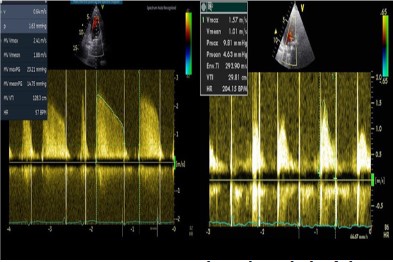

We present the case of a 52-year-old lady with Marfan syndrome, permanent pacemaker, Mitral Valve (MV) repair at the age of 34 years old and mitral valve replacement with a mechanical bileaflet prosthesis at the age of 40 yo who was referred to our Emergency Department (ED) for exertional dyspnea. Approximately 2 months prior due to exhibition fatigue and shortness of breath she was advised to undergo molecular COVID-19 test which was positive. She gradually deteriorated and was admitted in a COVID dedicated hospital. She was treated for coronavirus disease 2019 (COVID-19)-related pneumonia and was discharged ten days later. A month later she was referred to the ED of our hospital because of exertional dyspnea and palpitations. On the admission the ECG showed atrial fibrillation associated with a ventricular rate of 90-110 beats per minute. There were no signs of pulmonary edema in lung x ray. A Transthoracic Echocardiogram (TTE) revealed signs of prosthetic MV stenosis and elevated Right Ventricular Systolic Pressure (RVSP). The left ventricle was slightly dilated with moderate function. One of the discus of the mitral prosthesis was immobilized in closed position resulting obstruction to flow. The mean pressure gradient by Doppler echocardiography was 15 mmHg (Figure 1A) and the RVSP 70 mmHg. The International Normalized Ratio (INR) on admission was 2.6 and no problem with the INR therapeutic range was reported by the patient in the last months. The patient was initially treated with unfractionated heparin infusion. Follow-up TTE on second, fourth and sixth day later did not show signs of improvement.

A cardiac Computer Tomography (CT) examination revealed signs of discus thrombosis, a large thrombus on the anterior surface of the left atrium near the Left Atrial Appendage (LAA) and no coronary artery disease. The patient underwent a cardiac surgery in which thrombus from the LAA and the discus was removed and the LAA was sutured (Figure 2). After surgery the mean pressure gradient of the mitral prosthesis measured by Doppler echocardiography was decreased (4.6 mmHg) and there was no dysfunction of the discus (Figure 1B). Six days later the patient was discharged home.

Figure 1: Mean pressure gradient (Doppler) of the mechanical mitral valve before (A) and after (B) surgical removal of thrombus on the valve discus.